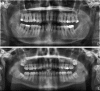

Periodontitis is a common chronic inflammatory disease characterised by destruction of the supporting structures of the teeth (the periodontal ligament and alveolar bone). It is highly prevalent (severe periodontitis affects 10-15% of adults) and has multiple negative impacts on quality of life. Epidemiological data confirm that diabetes is a major risk factor for periodontitis; susceptibility to periodontitis is increased by approximately threefold in people with diabetes. There is a clear relationship between degree of hyperglycaemia and severity of periodontitis. The mechanisms that underpin the links between these two conditions are not completely understood, but involve aspects of immune functioning, neutrophil activity, and cytokine biology. There is emerging evidence to support the existence of a two-way relationship between diabetes and periodontitis, with diabetes increasing the risk for periodontitis, and periodontal inflammation negatively affecting glycaemic control. Incidences of macroalbuminuria and end-stage renal disease are increased twofold and threefold, respectively, in diabetic individuals who also have severe periodontitis compared to diabetic individuals without severe periodontitis. Furthermore, the risk of cardiorenal mortality (ischaemic heart disease and diabetic nephropathy combined) is three times higher in diabetic people with severe periodontitis than in diabetic people without severe periodontitis. Treatment of periodontitis is associated with HbA(1c) reductions of approximately 0.4%. Oral and periodontal health should be promoted as integral components of diabetes management.